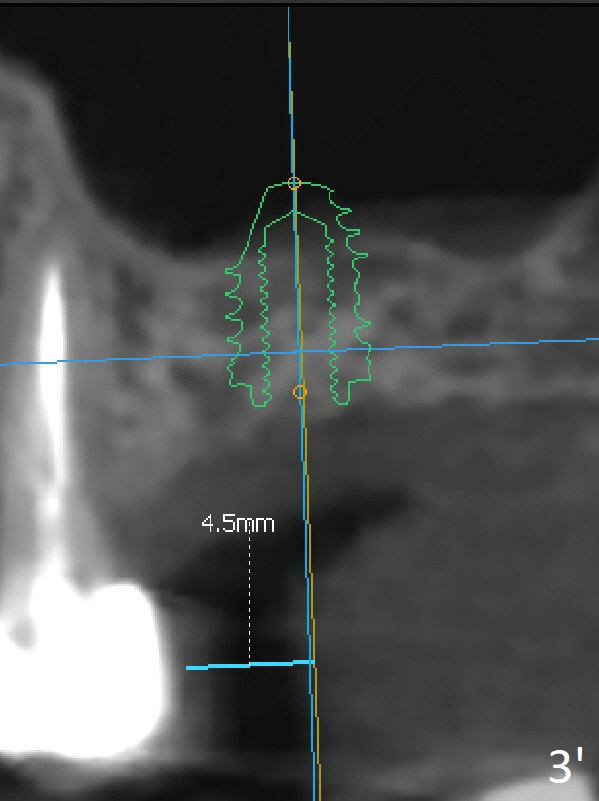

Two of 5x8.5 mm implants are placed at #2 and 3 with sinus lift using water ballooning technique; to avoid invading the neighboring root tips, an intraop PA is taken with a 2.2x11.5 mm drill at #5 (Fig.1). When a 2.5x11.5 mm 1-piece implant is placed at #7, there is 2.4 mm clearance from the impacted tooth (Fig.2). Following 1 mm deeper placement of the 1-piece implant, CT is taken to make sure that the threads are completely covered palatally (Fig.5 P). Interesting is that the sinus membrane is thickened at #2 and 3 (Fig.3 M), as compared to the clear sinus before surgery (Fig.3'). Bone graft is limited in the sinus (Fig.3 arrowheads). The implant at #5 (3.5x11.5 mm) is precisely placed subcrest bucco(B)-palatally (Fig.4). Since the limited field viewed CT does not cover the implant at #2 (Fig.3), immediate postop PA is taken (Fig.6). In fact all of the implants are placed subcrestal, as shown by intraoral X-ray 4 months postop (Fig.7-9). The abutments at #2, 3 and 5 are retorqued (30 Ncm) after crowns' try in and adjustment (Fig.10,11). There is a vertical gap between the implant and abutment at #2 (Fig.11 ^) and a horizontal one at #5 (<). There is apparently no bone loss 1 year 5 months post cementation (Fig.12).